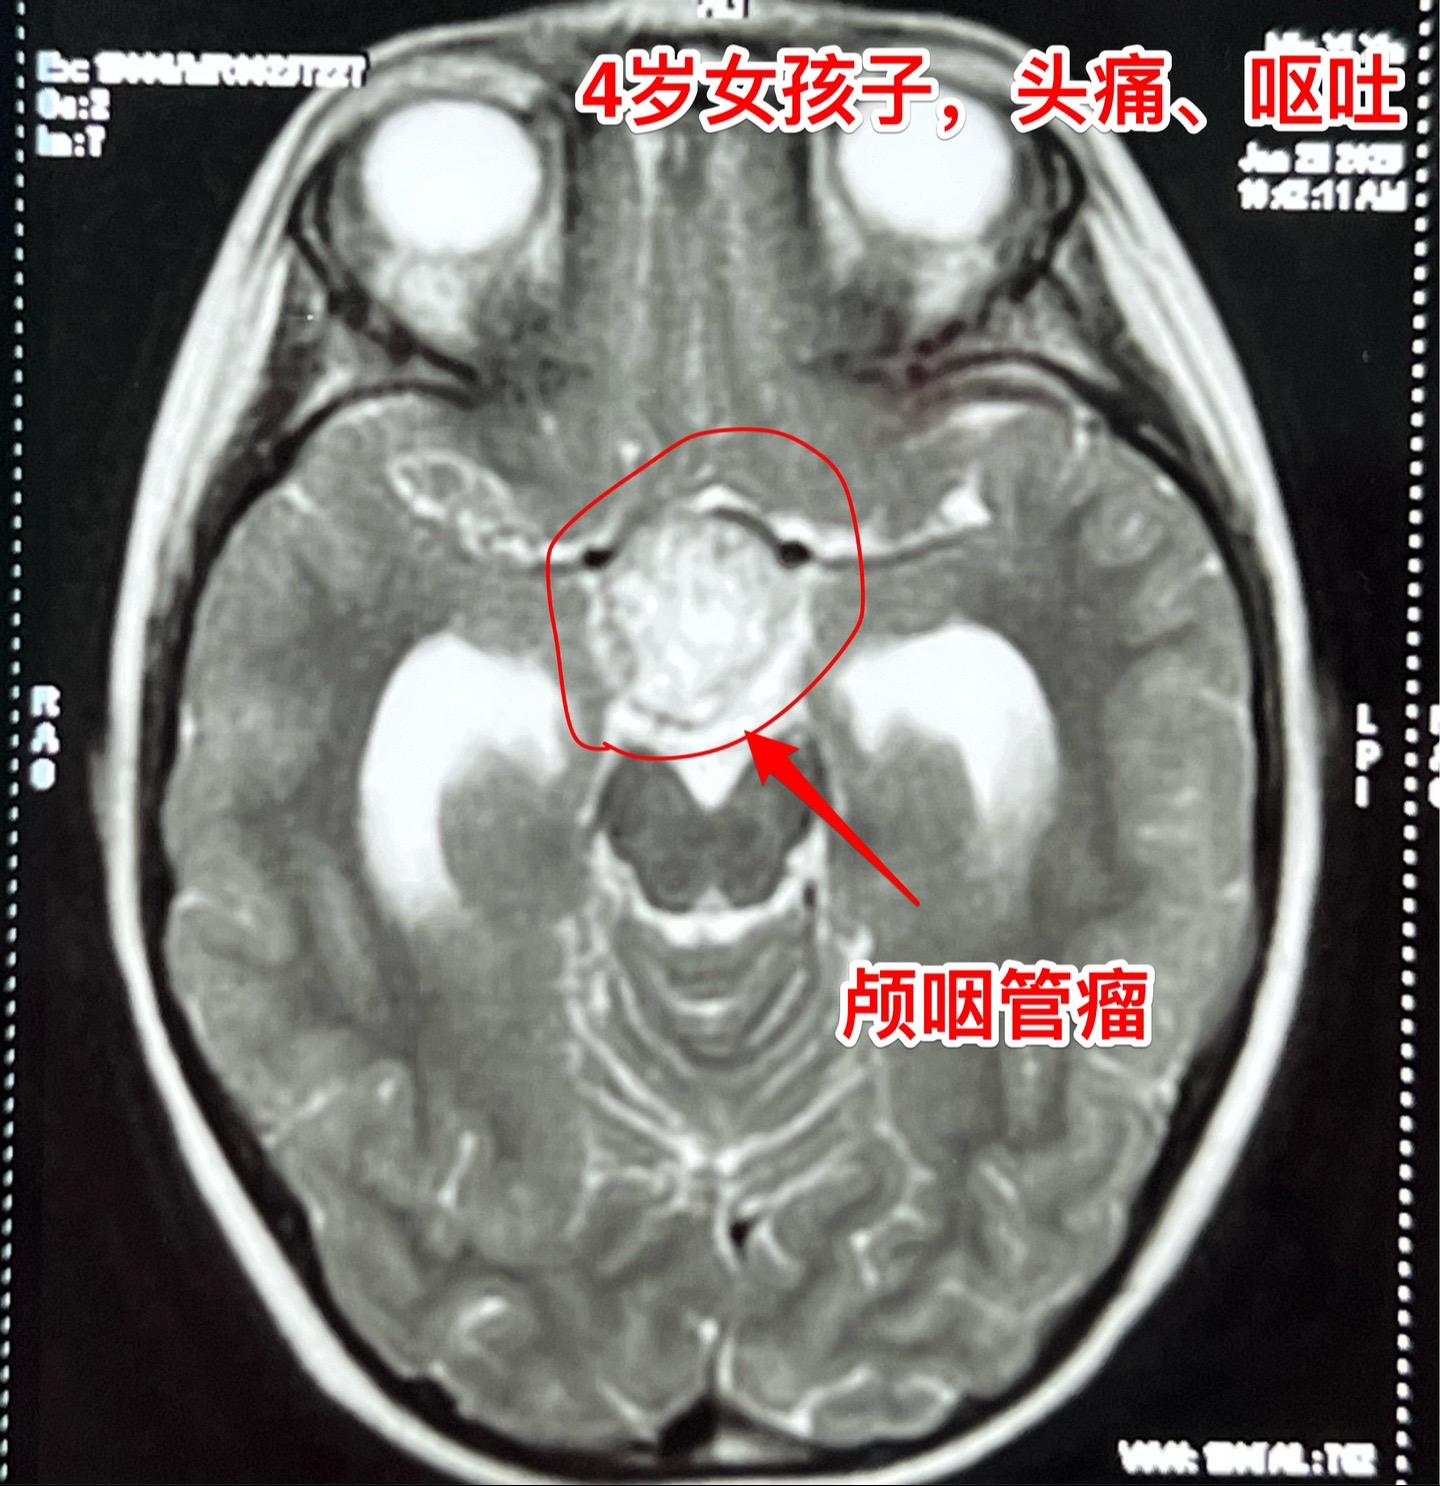

除夕当天发现颅咽管瘤,正月初七到三博住院。西安市的四岁女孩子,一个月前就开始出现头痛、间断出现呕吐,病情越来越严重,于1月28日就是除夕当天,在西安市行磁共振检查发现颅咽管瘤,伴有脑积水! 简直就是晴天霹雳! 在传统佳节里孩子的一家人处于诚惶诚恐之中。孩子头痛伴有呕吐,在当地医院每天都要输入甘露醇才能减轻症状。 正月初七一家人到三博脑科医院来住院。 正月初八正式上班,小孩子仍然有颅高压症状! 正月初九作了开颅手术,顺利切除